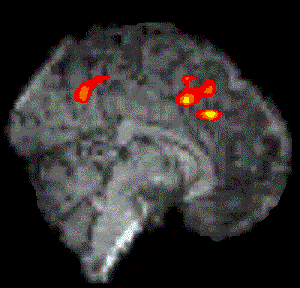

Figure 7.7 shows the activation at 0 s, 3 s, 6 s and 9 s following the stimulus, for one subject in the 'go, no-go' experiment. Maximum activation occurs at 3-6 seconds from the delivery of the stimulus. During the 'no-go' task, activation was seen in the medial premotor cortex for all the subjects. This region was rostral to the anterior commissural (AC) line. Activity was observed in these regions during the 'go' task as well (see Figure 7.8). During the 'go' task activation was also seen in a region of the premotor cortex caudal to the AC line.

Figure 7.8 View of the medial surface of the left hemisphere, three seconds after the stimulus in a go, no-go paradigm.

The mean value of the percentage change upon activation of the areas involved in the motor task are shown in Figure 7.9. This shows the rostral part of the premotor cortex (labelled pre-SMA) to be active in both 'go' and 'no-go' tasks, with the caudal part (labelled SMA) being only active in the 'go' task. This suggests that the pre-SMA is involved in the movement decision making aspect of the task, whereas the SMA proper is more intimately involved in the movement itself.